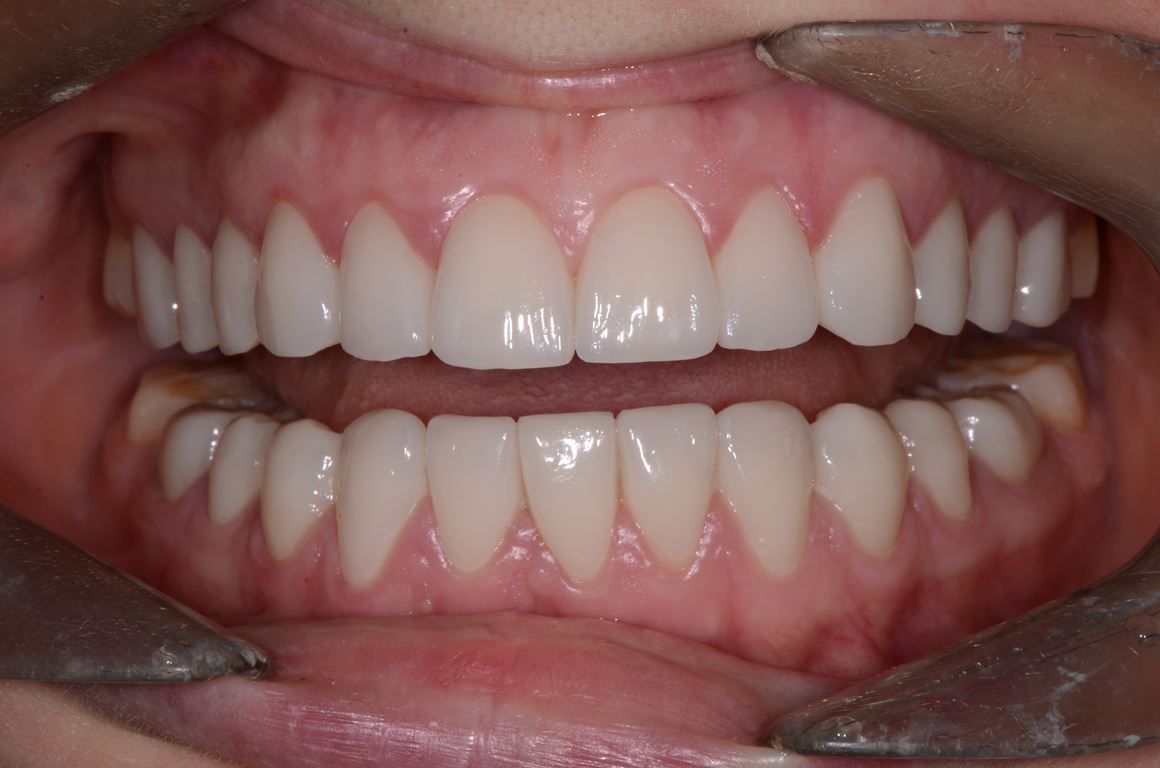

Ryciny 39-50 przedstawiają stan po zakończeniu leczenia.

Drugie zęby trzonowe nie zostały włączone w rekonstrukcję pomimo znacznej utraty wysokości koron. Dzięki temu podniesienie wysokości zwarcia mogło być zminimalizowane oraz uniknięto konieczności preparacji zniszczonych powierzchni zwarciowych tych zębów. Po przebudowie warunków zwarciowych na pozostałych zębach uzyskano prowadzenie przednie i kłowe, co potencjalnie dało ochronę zębów trzonowych przed destrukcyjnymi siłami bocznymi.